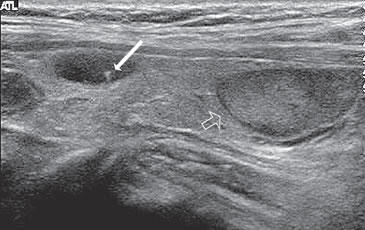

Figura 2. a) Quiste coloideo anecogénico y focos ecogénicos (flecha) con artefacto en cola de cometa; b) Nódulo mixto sólido-quístico (cabezas de flechas). Imagen vegetante (flecha) adherida a un tabique que se proyecta al lumen; c) Comparación entre el aspecto ecográfico de un cáncer papilar sólido (flecha abierta) y un quiste coloideo anecogénico.